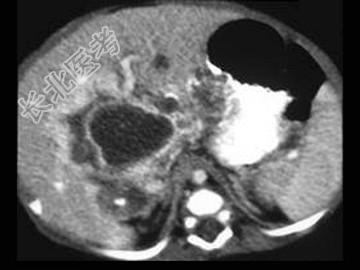

- 单项选择题男,39岁, 进行性消瘦、肝区不适、皮肤巩膜黄染2月,乙肝全套: HbsAg(+),Anti-Hbe(+), Anti-HbcIgG(+),肝功能及AFP均正常, CT检查如图,最可能的诊断是 ( )

A、肝脓肿

B、肝血管内皮瘤

C、肝血管瘤

D、胆管细胞癌

E、肝淋巴管瘤